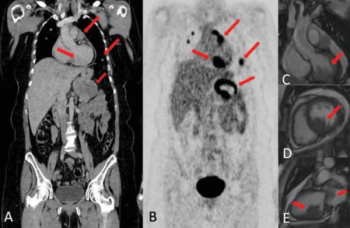

This clinical quandary discusses oligoprogressive disease in metastatic melanoma and how treatment with immunotherapy and targeted therapy affect the disease.